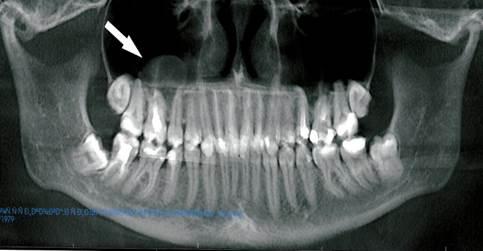

Рис. 3. Ортопантомограмма верхней и нижней челюстей. Стрелкой указано округлое новообразование мягкотканной плотности в правой гайморовой пазухе.

Во второй группе в одном клиническом случае новообразование находилось в области дна и медиальной стенки правой верхнечелюстной пазухи, а в другом — в той же области, но уже с обеих сторон. Первое округлое образование имело мягкотканную плотность, с ровными контурами и диаметром 17 мм, во втором случае размер превышал 20 мм.